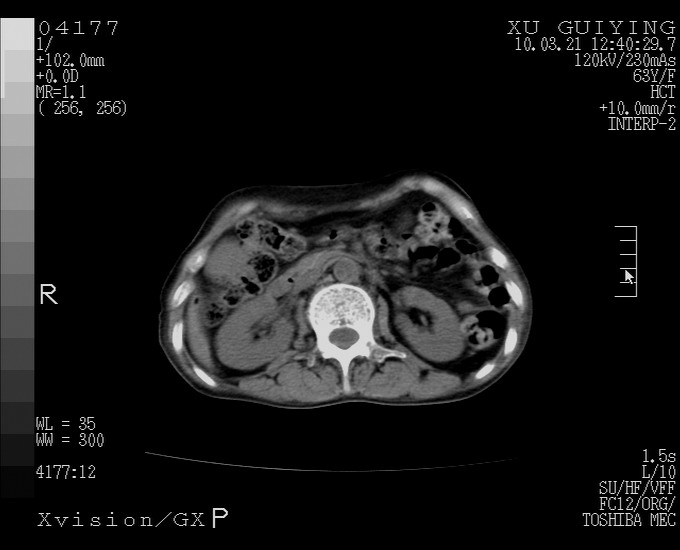

怎么没有增强呢?胆囊那么大,密度有些高啊。

慢性胆囊炎,胆囊占位不排除,建议增强或彩超。

考虑胆囊炎 不除外泥沙样结石

胆囊体积增大,胃窦壁增厚

胆囊体积增大,密度不均匀,结石不除外;胃壁增厚,考虑胃癌,建议增强。

胆囊体积增大,密度增高,较均匀,外缘也较光滑,应考虑胆囊炎。因为胃未充盈,不好说壁增厚。肝左叶及脾门处见低密度灶,有可能是血管瘤,不排除囊肿。建议超声检查或强化。